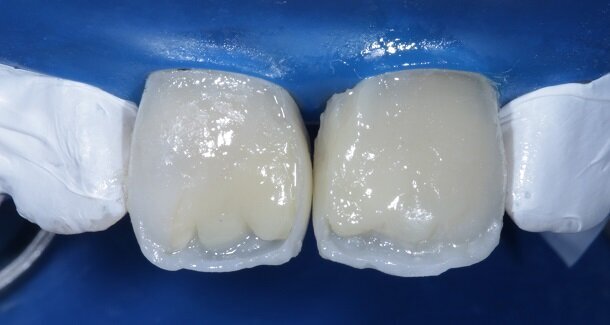

The figures show the clinical work flow involved. In the 1st appointment Oral prophylaxis, oral hygiene instructions were followed by an impression that was sent to the lab for a wax up [Fig 3 and 4]. In the subsequent appointments, Endodontic treatment was followed by Intra and extra coronal office bleaching using the Pola office bleaching kit. After two weeks, the shade stabilised post bleaching. Shade selection, rubber dam isolation and preparation was done on both the teeth to receive Direct composite veneers so as to close the midline diastema as well as correct the fractured teeth and the slight mal-alignment. Controlled Body Thickness (CBT) technique of layering was used with 3M Z350XT shades - Dentin shades A3, A2 and Enamel shades A2, clear translucent [Figures 5 to 11]. This was followed by the Finishing and polishing protocol as described in the figures.

Fig 12- Gross finishing for the outline of the tooth was achieved using Red ring (composite finishing) tapered rounded bur. Almost 80% of the finishing can be done using this bur. It also helps in creating surface macro and micro anatomical variations. For better control, this bur can be used on a contra-angled hand-piece along with a convertor.

Fig 13 and 14 -Transitional Line angles were marked using a pencil and made prominent using medium grit 3M Soflex Discs proximally. The apparent faces of both the teeth were thus, created.

Fig 15 and 16 - For the surface texture; vertical surface macro-anatomy showing developmental grooves (mesial and distal) were marked using a pencil and created using the red ring finishing bur.